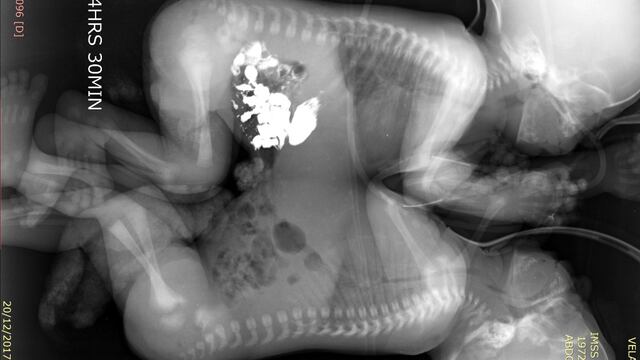

Tras diversos exámenes de tomografía, ecocardiograma y resonancia magnética, a los 41 días de vida, los niños fueron programados para la cirugía que los separaría.